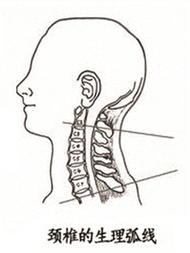

非洲原始部落女性,像这样头顶水壶,脖子伸得很直。 上周,第58届格莱美颁奖典礼落幕,美国女歌手泰勒·斯威夫特,这位身高一米八的金发美女一举拿下“年度专辑”等3项大奖。就在前几天,有微信公众号推送一篇文章,指出泰勒有致命缺点——脖子向前伸。 文章说,泰勒的脖子总是往前倾,头颈部和身体呈一定角度。 不过,有研究人员发现,现代人群中,有点脖子向前倾的人还不少。 有研究人类原始姿势的学者Esther Gokhale认为,从远古时期的雕像来看,老底子的人类站立时,脖子都是直的。 Gokhale去了非洲原始部落,观察那里人群的姿态。那里的女性,头顶水壶,脖子伸得很直,全身也是笔直的。她认为,正是因为这些女人颈部姿势正确,才能头顶水壶之类的重物而不会伤到颈椎。 为什么现代人看起来脖子向前倾?Gokhale分析,这与人们久坐不动的时间增加,经常低头看东西有关,“人们缺乏抬头、撑起脖子看远处的活动,所以脖子不自觉地向前伸了。” 这位专家的解释有无道理,我们自己的脖子情况怎么样? 脖子向前伸,是不是一定有颈椎病? 我们在办公室随机做了个小调查,看有多少人的脖子是向前伸的。 25位同事中,基本是三十岁以下的年轻人,昨天下午两点,23位同事坐在电脑前办公。一个个看过来,发现只有三位女同事的脖子没有前伸。 脖子向前伸,是不是一种病? 浙江大学医学院附属第一医院骨科主任林向进主任医师说,脖子向前伸,要分两种情况,一种是生理性的,一种是病理性。 生理性的,人的脖子本来就有韧性,向前向后都可以,经常保持一种姿势,人体习惯了这个体位,脖子就呈向前伸的状态。如果注意一下,人体立即可以恢复正常姿势。 病理性的,就是有颈椎病了,颈椎正常的生理曲度有了改变。正常的颈椎曲度是向前凸的,像一个“(”(见下图),而病理性的曲度变直,甚至反向成为“)”。姿态不太好看,像“乌龟向前伸头”。 “判断颈椎有没有变直或者反弓,不是用肉眼看看就行的,需要拍一张X光片,看清楚每根颈椎和椎间盘的排列。”林向进主任说。

正常的颈椎生理弧线 正常的颈椎有一个凸向前方的生理曲度,生理曲度消失的最初原因是颈部肌肉疲劳,累积到一定程度,颈椎椎间盘病变,椎间盘膨出,压迫神经,就会出现疼痛、胸闷和头晕的颈椎病症状了。 门诊中颈椎病年轻患者增多 他们的脖子也是向前伸 林向进主任医师说,门诊中的颈椎病患者有不少是脖子向前伸的,固定一个姿势,让他们脖子竖起来,都会喊疼。 省中山医院推拿科专门看颈椎病和腰椎病,科室主任吕立江教授说,门诊中超过一半的患者是来看颈椎病的,相对来说,颈椎比腰椎更容易受伤,颈椎附近的肌肉比腰椎要少,更容易受到不良姿势的影响。 本来颈椎病是种“退行性病变”,年纪大了,身体器官用得久老化了,发生了病变。“可现在年轻人得颈椎病的越来越多,主要是他们不注重颈椎健康,保持不良姿势,颈椎提前老化,得了颈椎病。” “最近,有个17岁的学生患者,到我们这里看颈椎,他的样子很特别,头向左前方伸出,好像跳街舞时被定格了。”吕主任说。 寒假就要结束了,他和爸妈约定,最后放松一下:连续三天,他都在夜以继日玩游戏——白天电脑游戏,晚上躲在被窝里玩手机游戏、看视频。前天,骑电动车上同学家玩,被冷风一吹,在一个街口转弯时,脖子被“卡牢”了。 吕主任说,这位学生的颈椎病其实还算轻的。“一直保持一个姿势玩电脑、手机,颈部肌肉劳损了,冷风一吹,肌肉僵硬,这还不是颈椎的问题。如果一直按现在的频率折腾颈椎,颈椎间盘突出等严重的颈椎病,迟早会找上门。” 林主任看门诊有这个感觉,“年轻的颈椎病患者越来越多,他们大多也是喜欢玩电脑、手机。” 浙江大学医学院附属第二医院骨科陈其昕教授说,门诊中经常有会计、文案、IT行业的患者,颈椎病算是他们的职业病。“现在智能手机越来越普及,又有一些新工种加入,比如手机App开发师、手机游戏开发师、微信编辑等。” 颈椎病患者中,手机族比电脑族的病情更有特点,“看手机,头低得更厉害,还合并腱鞘炎;电脑族则比手机族多了腰痛,颈椎不好,腰椎也不好。” 颈椎变形 能恢复到正常生理曲度吗? 陈其昕教授说,颈椎生理曲度,医学上把通过X光片上颈椎向前的弧形凸起称为“颈椎生理曲度”。颈椎生理曲度的存在,能增加颈椎的弹性,减轻和缓冲重力的震荡,防止对脊髓和大脑的损伤。由于长期坐姿、睡姿不良和椎间盘髓核脱水退变,颈椎的前凸逐渐消失,甚至变直或呈反张弯曲,即向后凸,这是颈椎病通过X光片诊断的重要依据之一。 “早期的颈椎弧度变直,仅仅是一个颈椎肌肉疲劳的信号,如果不当回事,颈椎仍旧超负荷工作,积累到一定程度,就会发生颈椎病。” 如果患者出现心慌、胸闷、头晕等交感神经症状,症状越来越顽固,这时颈椎弧度改变就不是单纯的肌肉疲劳信号,而是神经交感型颈椎病的表现;如果颈椎弧度变直并有肢体麻木、胳膊疼痛、走路踩棉花感等脊髓压迫的表现,应该到医院做个颈椎核磁共振检查,是否合并有脊髓型或神经根性颈椎病的可能。 “大家照镜子、拍X光片,发现颈椎生理曲度改变,不要惊慌,不要以为脖子变直了就一定是颈椎病,如果是早期的肌肉疲劳,稍微改变一下坐姿习惯,颈椎的生理弧度会慢慢恢复正常,不会恶化成颈椎病。”陈教授说。 怎么保护颈椎? 试试专家的“仙鹤点水”操 远离颈椎病,应注意两点:一是改变不良姿势,二是,坚持多活动。 怎么活动?大家熟悉的“米字操”,在专家看来,要因人而异。“有些椎间盘型的颈椎病患者,不能做旋转型的运动,不能动得太快,否则,做了反而会加重病情。”林向进主任说。 省中山医院的吕立江教授有套颈椎保健操,几个动作,锻炼颈椎。吕教授经常在门诊里教患者做,大家反响不错。